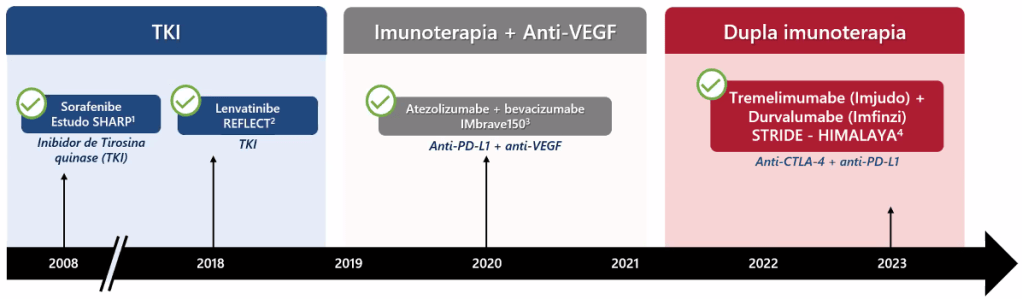

Hoje temos diversos tipos diferentes de quimioterápicos para o hepatocarcinoma. Os inibidores da tirosinoquinase (sorafenibe, lenvatinibe, regorafenibe e cabozantinibe) foram considerados até hoje a primeira linha de tratamento sistêmico, mas com resultados não muito animadores. Os imunobiológicos, que agem em pontos mais específicos, tendem a ser melhor tolerados e ter melhor resposta, deixando de ser usados isoladamente para agora ser indicados em duplas.

A dupla “atezo-bevo” (atezolizumabe com bevacizumabe) pode hoje ser utilizada como primeira linha no tratamento sistêmico, mas está contraindicada em pacientes com varizes esofágicas não tratadas pelo alto risco de hemorragia. Outra combinação potente que compete pelo status de primeira linha é tremelimumabe com durvalumabe.